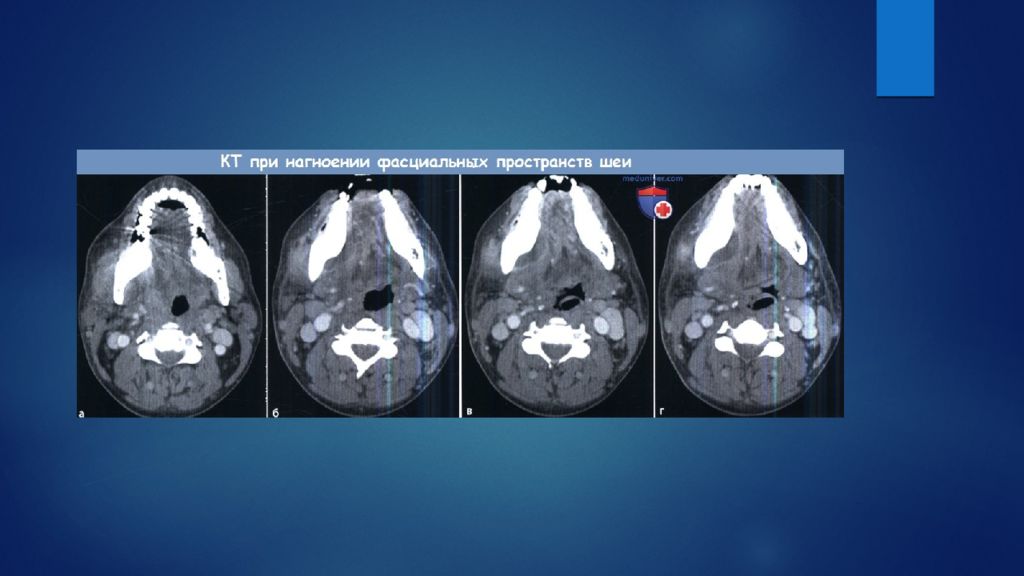

Мскт мягкие ткани

Мскт мягкие ткани 116 фотографий